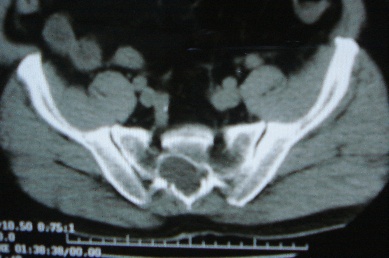

以下是引用zhangzhongshou在2007-6-17 11:53:00的发言:[br]骶管囊肿可能性大,建议mri检查。

以下是引用jinguoji在2007-6-17 14:53:00的发言:[br]骨质未见确切破坏,考虑骶管囊肿可能性大,建议mri检查。